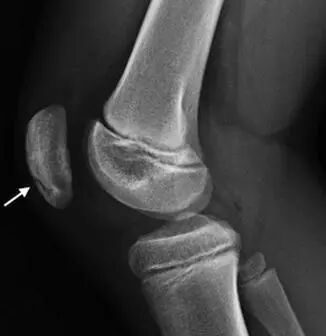

髌骨的骨化变异情况很常见。已骨化的髌骨可能呈颗粒状或结节状;它可能存在硬化区和透亮区。前方的透亮区以及前方表面的横向和纵向嵴尤其常见。垂直裂隙最为常见(图1)。

图3 髌骨下极存在撕脱性骨折(长箭头所示)。可见轻度软组织肿胀。髌骨前方的高密度影是一个骨化中心(箭头端所示)。